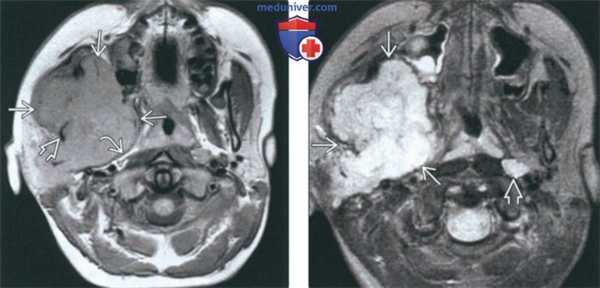

(Слева) На аксиальной КТ с КУ в жевательном пространстве справа визуализируется злокачественная фиброзная гистиоцитома нижней челюсти в виде минимально контрастирующегося солидного объемного образования, разрушающего ветвь и тело нижней челюсти. Жевательное пространство является известным местом возникновения сарком глубоких областей ли ца.

(Справа) На аксиальной КТ с КУ у этого же пациента визуализируется опухоль в жевательном пространстве справа, приводящая к обширной деструкции нижней челюсти. Обратите внимание на асимметрию лица на стороне поражения.

(Слева) На аксиальной МРТ (Т1 ВИ C+) в жевательном пространстве визуализируется лейомиосаркома высокой степени злокачественности, неравномерно накапливающая контраст и поражающая нижнюю челюсть. Большинство типов сарком жевательного пространства сложно дифференцировать в отсутствие костного или хондроидного матрикса.

(Справа) На корональной МРТ (Т1 ВИ С+ FS) у этого же пациента визуализируется контрастирующаяся опухоль с интракраниальным распространением через овальное отверстие а и поражением кавернозного синуса.

(Слева) На аксиальной МРТ (Т1ВИ) в жевательном пространстве визуализируется саркома Юинга в виде огромного объемного образования с гиперинтенсивным относительно мышц сигналом. Ветвь нижней челюсти разрушена, на этом изображении виден лишь ее мелкий фрагмент. Полоска окологлоточного жира смещена кнутри.

(Справа) На аксиальной МРТ (Т2ВИ FS) у этого же пациента определяется неоднородный сигнал крайне высокой интенсивности в опухоли. Хорошо различимый заглоточный лимфоузел слева является случайной находкой.